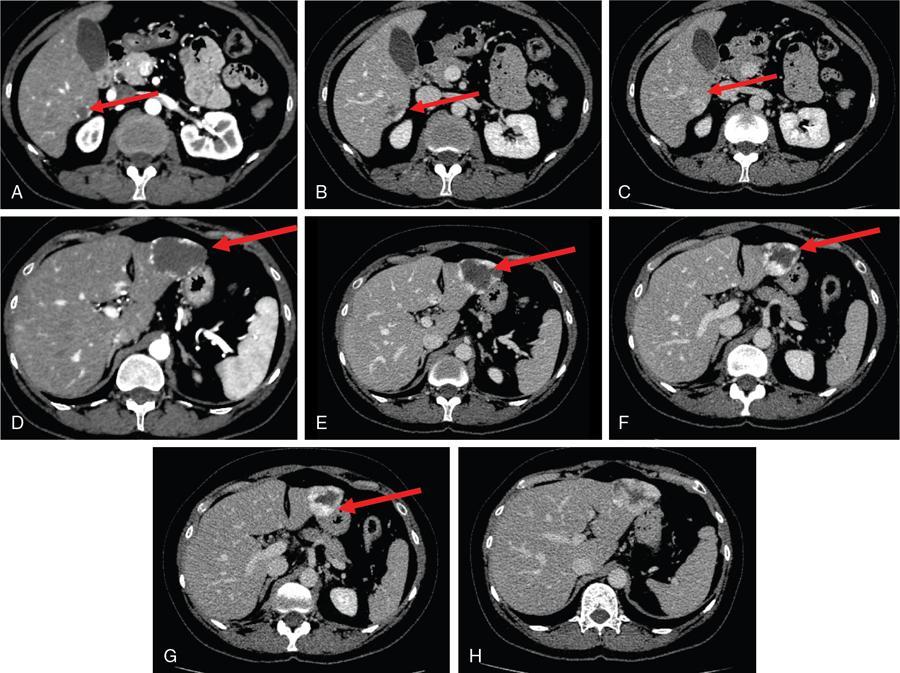

Ritu K. Kashikar, Shrinivas B. Desai, Pooja Punjani Vyas, Nilesh Doctor, Vivek Shetty Owing to advances in technology, focal liver lesions (FLLs) are increasingly encountered. Imaging particularly computed tomography (CT) and magnetic resonance imaging (MRI) play a vital role in diagnosis and characterization of FLL, thus avoiding unnecessary biopsies and interventions. Multiphase CT accurately diagnosis most liver lesions. Better soft tissue contrast and lack of ionizing radiation makes MRI a preferred modality in diagnosing FLLs. MRI with or without contrast for characterization of liver lesions regardless of preexisting liver disease has been assigned the highest rating as per American College of Radiology Appropriateness Criteria (Table 9.11.1). Solid lesions of epithelial origin Solid lesions of nonepithelial origin Pitfalls Cystic liver lesion Developmental cyst Infective cyst Miscellaneous Tmours of hepatocellular origin Tumours of nonepithelial origin Malignant cystic lesion Hepatic metastasis Ultrasound is often the initial modality for diagnosis and also the incidental detection of FLLs. Limitations to USG include the detection of small lesions less than 2 cm in size, particularly in patients who are cirrhotic or undergoing chemotherapy. Characterization of FLLs, involvement of crucial structures such as blood vessels, local staging and decisions such as operability are also not accurate with ultrasound alone and require confirmation with CT/MRI. The liver typically images in supine and left lateral positions. A curvilinear transducer with a frequency of 1.5 Hz is used. The subcostal diagonal, subcostal longitudinal or sagittal and transverse right intercostal lateral views are used. Right lobe of liver is imaged through an intercostal approach when the patient is taking deep inspiration. Subcostal view is used to image the three hepatic veins in one view. Transverse, longitudinal and oblique views of the liver are taken to image all the segments of liver. Colour and power Doppler have increased sensitivity for FLL detection, but sensitivity is still inferior to contrast-enhanced CT and MRI. The introduction of microbubble contrast agents (CAs) and the development of contrast-specific techniques have opened new perspectives in ultrasound of the liver. The technique is based on a new class of intravascular microbubble agents which contain perfluoro gases instead of air. This when combined with scanning modes sensitive to harmonic responses of microbubbles enable tissue signal suppression. The advent of the multislice technique and isotropic voxel have improved the spatial resolution of CT, allowing the recognition of small FLLs in difficult areas. Multislice CT has a sensitivity and specificity in the diagnosis of malignant FLLs of 63% and 64%, and 92 and 97%, respectively. Contrast media administration with dose based on the patient’s weight (approximately 600 mg iodine/kg of bodyweight), an iodine content of 350–400 mg/mL and a high injection rate of 4–5 mL/s are imperative to attain good contrast enhancement. Region of interest in the abdominal aorta and a threshold of 100 HU allows correct timing for threshold. A delay of approximately 18 s after the threshold provides the first arterial phase, allowing detection of hypervascular FLLs such as hepatocellular carcinoma (HCC). The late arterial phase is obtained approximately 10 s after the early arterial phase and shows progressive enhancement of hypervascular lesions, improving detection rate, while the optimal hepatic enhancement in the portal phase is reached approximately 50–60 s after the threshold. Portal venous thrombi are also best detected in this phase. The venous phase aids in the detection of washout, hepatic venous thrombosis. Delayed phase is often required in lesions such as cholangiocarcinoma and haemangioma, which show progressive enhancement (Table 9.11.2, Fig. 9.11.1). Delayed phase images are required for tumours such as cholangiocarcinoma and large haemangiomas, which reveal delayed enhancement. As mentioned previously, MRI is the modality of choice in diagnosis of FLLs. Most FLLs appear hyperintense on T2W1 images with varying intensity depending upon the water content and flow dynamics. FLLs are typically hypointense on T1W1 images with the exception of fat containing, haemorrhagic lesions and those containing chelates of metals like regenerating/dysplastic nodules. In- and opposed-phase images help in detection of intralesional fat. Diffusion-weighted images are beneficial particularly in noncirrhotic population and best suited in detection of metastasis. Postcontrast images obtained with extracellular agents are parallel to those obtained with CT (Fig. 9.11.2). The pre- and postcontrast MRI protocol is mentioned in Table 9.11.3. T2-weighted single-shot fast spin-echo (SE) T1-weighted in- and opposed-phase GRE Dynamic 3D T1-weighted FS spoiled GRE (in hepatic arterial, portal venous and equilibrium phases) There are two main categories of CAs used in liver imaging – the extracellular and the hepatocyte-specific (Fig. 9.11.3). Extracellular agents are more widely used and provide information similar to contrast-enhanced CT study. The advantage of the other category of CAs, that is, hepatocyte-specific agents, is the ability to provide this extracellular information with added benefit of delayed phase information. Tumours of hepatocellular origin with functioning hepatocytes take up and biliary excretion with take up and retain these agents appearing isointense to background liver. Lesions without functioning hepatocytes fail to retain contrast and hence appear hypointense to background liver on delayed phase. This allows better detection and characterization of focal liver lesion particularly those lesser than 2 cm (Table 9.11.4). Haemangioma is the most common benign hepatic tumour. The incidence in general population varies from 1% to 20%. Females have a higher preponderance with variable female to male ratios of 2:1 to 5:1. Imaging in particular MRI has high reliability in diagnosing classic haemangioma. The sensitivity and specificity of MRI is greater than 90% in diagnosis. The aetiology of haemangioma is unknown. Since haemangiomas are known to run in families, a genetic origin has been implicated, while other mesenchymal tumours are thought to be congenital. Most patients are asymptomatic and often the lesion is discovered as an incidental finding. Pain in the right upper abdomen is the most common complaint; others include loss of appetite, nausea, vomiting and abdominal discomfort. Symptoms are usually seen in large haemangiomas or those with complications. Liver function tests and tumour markers like AFP and CA19.9 are within normal limits. Blood-filled cavities of varying sizes lined by flat endothelial cells and supported by fibrous connective tissue are seen on histology. Three histological subtypes have been described: the capillary haemangioma, the cavernous haemangioma and the sclerosing haemangioma. The imaging features of a haemangioma depend on its size; typical haemangiomas are mostly less than 3 cm in diameter. Haemangiomas are hyperechogenic, homogeneous lesion presenting a posterior acoustic enhancement (Fig. 9.11.3). The hyperechogenicity of haemangiomas is related to the interfaces between vascular spaces, fibrous stroma and the slow blood flow. Typically, haemangiomas have slow flow and hence do not show vascularity on colour or power Doppler. The sensitivity and specificity of ultrasound in differentiating haemangioma from other malignant lesions are high, with values of approximately 94.1% and 80%, respectively, for lesions less than 3 cm in diameter. Unlike HCC, no flow is seen on colour Doppler. A peripheral echogenic rim around hypoechoic lesions can suggest haemangioma. On the contrary, perilesional hypoechoic rim called the target sign is seen in lesions such as metastasis (Table 9.11.5). Adenomas can be distinguished on the basis of the absence of posterior acoustic enhancement and characteristic pattern of peripheral vascularity seen in adenoma. Another differential diagnosis to be considered is focal nodular hyperplasia (FNH), which has the characteristic ‘spoke-wheel sign’. Contrast-enhanced ultrasound (CEUS) improves specificity for the diagnosis of haemangioma. The vascularity pattern with contrast-enhanced USG is similar to that seen with CT. The typical hemangioma (HH) shows peripheral nodular enhancement in the arterial phase with complete (but sometimes incomplete) centripetal filling in the portal venous and late phases. This particular pattern of enhancement helps in differentiating haemangiomas from other lesions like adenomas, FNH, HCC or metastasis. This characteristic enhancement pattern has a sensitivity of 98% for histologically proven HH. One should be aware that an HH can rarely have a centrifugal enhancement. Computed tomographic (CT) findings consist of a hypoattenuating lesion on nonenhanced images. Haemangiomas show peripheral discontinuous nodular enhancement on arterial phase of dynamic contrast-enhanced CT. The density of the nodules is equivalent to that of the aorta. Centripetal filling with is seen on venous phase, which progresses to uniform enhancement. The enhancement persists on delayed phase (Fig. 9.11.4). Washout of contrast on delayed phase is not seen in haemangioma and if seen, alternate diagnosis must be considered. This classical pattern of enhancement cannot be highlighted in very small lesions of less than 5 mm, which can be difficult to characterize. In patients with severe fatty infiltration of the liver, HH can appear hyperdense relative to the adjacent liver parenchyma on nonenhanced scan. Haemangiomas are hyperintense on T2-weighted images, which is identical to that of cerebrospinal fluid. T2 hyperintense signal is classically described as ‘light bulb bright’. Malignant lesions of the liver do not appear as bright on T2W1 images. They appear hypointense to adjacent liver on T1-weighted images. Long relaxation T2W1 images further improve accuracy in diagnosis of haemangiomas and help in differentiation from metastasis. Haemangiomas, unlike other liver lesions retain hyperintense signal on long relaxation T2W1 images. A threshold of 112 ms has 92% accuracy, 96% sensitivity and 87% specificity for differentiating haemangiomas from metastasis. On gadolinium administration, the enhancement pattern is similar to that seen with iodinated contrast on CT. Classic enhancement pattern in combination with characteristic T2 appearance are diagnostic for haemangioma (Fig. 9.11.5). Certain pitfalls exist in diagnosing haemangiomas using gadoxetate disodium. Due to the lack of hepatocytes, haemangiomas appear hypointense to the background liver on delayed hepatocyte phase and mimicking malignant process (Table 9.11.6). Lesions shown peripheral nodular arterial enhancement (Table 9.11.7): On fluorodeoxyglucose-positron emission tomography (FDG-PET)/CT, most hepatic haemangiomas appear low-attenuation lesions with FDG avidity equal to background liver parenchyma and are easily determined to be benign. However, a small percentage of haemangiomas may be FDG-avid. If an FDG-avid hepatic lesion demonstrates the characteristic enhancement pattern, this is consistent with an FDG-avid haemangioma. Technetium-99m pertechnetate-labelled red blood cell scintigraphy has high specificity in the diagnosis of haemangiomas. In this technique, there is decreased activity in haemangiomas on early images and increased activity on delayed blood pool images. Therefore, radionuclide scintigraphy has a sensitivity of 78% and an accuracy of 80% and may be a valuable tool when the diagnosis cannot be achieved with other imaging modalities. Large haemangiomas are often heterogeneous with internal clefts and septae. They are termed as giant haemangiomas when they exceed 4 cm in diameter. Discrepancies are there in definition with some authors defining giant haemangiomas as lesions greater than 6 cm or 12 cm in diameter. These may cause symptoms of abdominal pain and distension. These haemangiomas demonstrate changes such as haemorrhage, thrombosis, extensive hyalinization, liquefaction and fibrosis. The central cleft-like area may be due to cystic degeneration or liquefaction. On USG, they reveal heterogeneous echotexture. They are hypoattenuating and heterogeneous on nonenhanced CT with central areas of low attenuation. After intravenous administration of contrast material, the typical early, peripheral and globular enhancement is observed. These may show irregular or ‘flame-shaped’ discontinuous peripheral enhancement as opposed to typical nodular enhancement pattern seen in smaller haemangiomas. Although centripetal pattern of enhancement is seen during the venous and delayed phases, the filling-in incomplete. Central scars are defined in this subset of haemangiomas (Fig. 9.11.6). At MRI, T2-weighted images show a markedly hyperintense cleft-like area and some hypointense internal septa within a hyperintense mass. On delayed phase, incomplete filling and central scar are seen similar to CT (Fig. 9.11.7). Complications include intratumoural haemorrhage, inflammatory changes or consumptive coagulopathy (Kasabach–Merritt syndrome). These may warrant management such as arterial embolization or resection. This pattern is seen 16% of all haemangiomas, and is seen more often in small haemangiomas (42% of haemangiomas) <1 cm in diameter. CT and MRI show immediate homogeneous enhancement at arterial phase CT or contrast-enhanced MRI. The size of the blood spaces is the reason for difference in enhancement pattern. Smaller the lesion, smaller the size of blood spaces and faster the rate of spread of contrast material. These lesions usually show perilesional halo of hyperenhancement on the late arterial phase, which is believed to be due to arteriovenous shunting. Rapid arterial enhancement makes these haemangiomas difficult to distinguish from hypervascular metastasis (Table 9.11.8). However, washout of contrast is seen from haemangiomas on delayed phase (Fig. 9.11.8). Hepatic haemangiomas rarely demonstrate calcifications, while haemangiomas in other locations frequently demonstrate phleboliths. Calcified haemangiomas are mostly found incidentally. Calcifications may occur in the marginal or central portion of the lesion and consists of multiple spotty calcifications, which correspond to phleboliths. However, large, organized calcifications are also possible. Some calcified haemangiomas may demonstrate poor enhancement. Hyalinized hepatic haemangiomas are rare. It has been suggested that hyalinization represents an end stage of haemangioma evolution. These haemangiomas are usually asymptomatic. The radiological features of a haemangioma are completely altered ones hyalinization occurs; hence biopsy is often mandatory for diagnosis. Hyalinized haemangiomas show only slight high signal intensity on T2W1 images. There is lack of early enhancement on dynamic contrast-enhanced images (Fig. 9.11.9). Fluid–fluid levels within haemangiomas are very rare. Fluid–fluid levels are seen both with CT and MRI with inferior layer representing the red blood cells and superior layer unclotted serous blood. Dependent hyperdensity/T1 hyperintensities can be seen corresponding with dependent haemorrhage. Pedunculated haemangiomas are very rare. They can be asymptomatic or complicated by subacute torsion and infarction. Typical enhancement pattern and signal on T1 and T2W1 images are clues to the diagnosis. Capsular retraction is usually associated with malignant tumours such as cholangiocarcinoma, epithelioid haemangioendothelioma or metastases. Rarely, it has been seen in haemangiomas. A possible mechanism could be fibrous degeneration. Multiple haemangiomas are seen in 10% of cases and usually show classical imaging features. Fatty infiltration of liver may alter the imaging appearances of lesions. Haemangiomas appear slightly hyperechoic, isoechoic or hypoechoic relative to the fatty liver. At nonenhanced CT, the lesion may be hyperattenuating relative to the liver. Contrast-enhanced CT shows peripheral enhancement and delayed filling, an appearance similar to that of a haemangioma in a normal liver. Haemangiomas are less common in setting of cirrhosis and may be difficult to diagnose due to sclerosis. Complications are seen in 4.5%–19.7% and often seen in large lesions such as inflammation, coagulation within can lead to systemic disorders, haemorrhage would lead to haemoperitoneum, volvulus and adjacent organ compression. Irrespective of the size, treatment is indicated only for haemangiomas with significant symptoms, those developing complications, or when there is an inability to exclude malignancy. Attempt should be made to exclude other causes of the patient’s symptoms. The term focal nodular hyperplasia (FNH) was introduced in 1958 by Edmondson. In 1995, the International Working Party classified FNH with other regenerative lesions, and not a neoplastic lesion. It is defined as a nodule consisting of normal appearing hepatocytes occurring in a histologically normal liver. It is the second most common tumour of the liver after haemangioma with a reported prevalence of 0.9%. The lesion is more commonly seen in females with female to male ratio of 8:1. Multiplicity is seen in 20% of patients. The combination of multiple FNH lesions and haemangiomas is considered to be multiple FNH syndrome. Vascular malformation and vascular injury have been suggested as the underlying mechanism. An association with steroids has been denied more recently. FNH has been classified as classic and nonclassic varieties. These have been discussed in Table 9.11.9. Classic FNH is characterized by abnormal nodular architecture, malformed vessels and cholangiolar proliferation. Nonclassic FNH lesions lack one of the following classic features – nodular abnormal architecture or malformed vessels – but always show bile ductular proliferation. Classic FNH on gross appearance shows lobulated contours with multiple nodules surrounded by fibrous septae originating from a central scar, which contains a vascular malformation. On histopathology, nodular hyperplastic parenchyma is seen in classic FNH. Circular or short fibrous septae surround these nodules completely or incompletely. Thickening of the hepatic plates is seen. Fibrous connective tissue, cholangiolar proliferation with surrounding inflammatory infiltrates and malformed arteries, capillaries, vascular channels of undetermined type and veins are seen in the central scar. The arterial blood in FNH shows centrifugal distribution from anomalous central arteries. Fatty infiltration is seen in approximately 50% of lesions, while signs of hepatic steatosis are seen in approximately 20% of cases with classic FNH. Variable amounts of Kupffer cells are seen in both classic and nonclassic variants. Nonclassic FNH is heterogeneous and on gross appearance resembles adenomas in most cases, with vaguely lobulated contours and lack of a macroscopic central scar. The histology varies with subtypes. Subtypes of nonclassic FNH include telangiectatic type, mixed hyperplastic and adenomatous forms and FNH with cytologic atypia. The histological features of these are described in Table 9.11.10. At US, typical FNH is often not well visualized. The lesions may be slightly hypoechoic, isoechoic or slightly hyperechoic. The compressed liver tissue form a hypoechoic halo around the lesion, which appears more prominent in patients with fatty infiltration. A prominent central scar may improve the conspicuity of the lesions. Use of colour and power Doppler US shows vascularity in suspected FNH. On contrast-enhanced USG, FNH is hyperenhancing in the arterial and portal venous phases in more than 90% of cases. The arterial enhancement patterns include central (60%–70% of cases) or eccentric (<20% of cases) with centrifugal filling, but sometimes are homogeneous. Multiphase CT is an excellent modality for detection and characterization of FNH. These lesions classically show a lobulated contour. At unenhanced CT, the lesions are either hypoattenuating or isoattenuating to the surrounding liver. In the arterial phase, the lesions show homogeneous intense enhancement except the central scar and fibrous septa. In the portal and later phases, the lesions become more isoattenuating with the surrounding liver. The central scar reveals enhancement on delayed phase (Fig. 9.11.10). This feature helps distinguish from other lesions with central scar-like fibrolamellar carcinoma. A vascular malformation can be seen in the central scar in some cases (Fig. 9.11.11). There may be enlarged hepatic veins in the vicinity of the mass. FNH do not have portal venous drainage. The drainage is essentially into hepatic venules, hence the enlarged adjacent veins. The central scar is often not identified in small FNH lesions. In a study, 80% of FNH lesions less than 3 cm lacked visible central scar. The sensitivity and specificity of MRI in diagnosis of FNH are 70% and 98%, respectively. The central scar is more often detected with MRI than with CT (78% and 60%, respectively). FNH is typically iso- or hypointense on T1-weighted images (94%–100%) and is slightly hyperintense or isointense on T2-weighted images (94%–100%). The lesions may not be very conspicuous on T2W1 images. The central scar is hyperintense on T2-weighted images in 84% of cases. FNH shows intense homogeneous enhancement in the arterial phase. The enhancement pattern in arterial phase may be nodular, resembling a popcorn, the result of intralesional fibrous septae. Mosaic pattern of heterogeneous enhancement seen in malignant lesions is not seen in FNH. Central vascular malformation may be seen in early phases. These lesions classically fade to isointensity on delayed phase with the exception of the central scar (Fig. 9.11.12). FNH may show a pseudocapsule, which results from compression of the surrounding liver parenchyma by the FNH, perilesional vessels and inflammatory reaction. The pseudocapsule may show enhancement on delayed contrast-enhanced images. A central scar is present at imaging in most patients with FNH. The central scar is hyperintense on T2W1 and hypointense on T1W1 images. The presence of inflammation and vessels within the scar are responsible for the hyperintense signal (Fig. 9.11.13). The scar does not enhance on early phases of contrast study and shows enhancement on delayed phases of dynamic study. The scar is absent in 30% of cases. The hepatocyte-specific CA gadoxetate disodium can be useful in distinguishing FNH from other lesions like adenomas. Densely packed functioning hepatocytes and abnormal blind-ending bile ductules in FNH result in contrast retention and delayed biliary excretion. FNH often shows enhancement on delayed images using gadoxetate disodium, and along with radiating fibrous septae, it may result in a characteristic spoke-wheel appearance. On the contrary, hepatocellular adenomas (HCAs) are usually hypointense to liver on hepatocyte phase images because they lack bile ductules. Superparamagnetic iron oxide (SPIO) is a negative reticuloendothelial-specific CA taken up primarily by the hepatosplenic Kupffer cells. This agent shortens T2 relaxation time predominantly, leading to a significant decrease of SI of normal hepatic. FNH contains Kupffer cells and hence shows significant signal drop after administering SPIO. This CA is, however, not commonly used particularly with advent and increased usage of hepatocyte-specific agents (Table 9.11.11). These lesions have high signal intensity on T2-weighted images, a central scar with low signal intensity on T2-weighted images, a prominent pseudocapsule and incomplete intense enhancement of the lesion. Extreme heterogeneity can be seen in these lesions leading to difficulty in distinguishing from malignant lesions such as HCC and cholangiocarcinoma. Biopsy and histopathology diagnosis are often needed in this subset. Telangiectatic FNH may show areas of haemorrhage. A French study has reported an association of 23% between FNH and haemangiomas. The incidence of coexistence of FNH and adenoma is lower (3.6%). There have also been reports of rare associations of FNH with other types of vascular anomalies like congenital absence of the portal vein, inflammatory pseudotumours of the liver, hepatic vein thrombosis and intrahepatic arteriovenous shunting. Imaging differentials include HCA and other lesions with central scar like fibrolamellar carcinoma, HCC and giant haemangiomas (Table 9.11.12). FNH shows intense arterial phase enhancement and isodensity/isointensity on delayed phase, this feature helps in distinguishing from adenoma, which usually are hypoattenuating on the delayed phase. T1 hyperintensity seen in adenomas is not seen on FNH. Biopsy is recommended in cases where radiological features are atypical and distinguishing from malignant lesions like HCC cannot be made on the basis of imaging findings alone. As there is no risk of malignant transformation and complications are rare, FNH does not need treatment. Patients with large FNH causing compression of adjacent organs or occurrence of torsion in a pedunculated FNH may need surgical resection. Also, patients with diagnostic dilemma may be considered as surgical candidates. Adenoma is a less common benign primary neoplasm of the liver. Women of childbearing age taking oral contraceptives are considered at highest risk; however, it can occur in other women as well as men. Hepatic adenomas (HAs) were particularly associated with the use of older generation of OC pills with high-oestrogen content. Adenomas have also been reported to occur in men secondary to anabolic steroid/androgen use. Clomiphene, danazol and testosterone in patients with Fanconi anaemia (FA) and without FA, Klinefelter’s syndrome, glycogen storage disorders (GSDs) I, III and IV, alcohol and metabolic syndrome are other hormonal therapies and conditions associated with adenoma. Development of >10 adenomas in a patient is defined as hepatocellular adenomatosis (Fig. 9.11.14). Germline mutations of hepatocyte nuclear factor (HNF)-1 alpha and patients with type 3 maturity onset diabetes of young (MODY-3) may predispose. HCA has been categorized into three distinct subtypes based on genetic and pathologic features. These have been discussed in Table 9.11.13. Some exhibit both β-catenin activation and inflammatory features. Patients are usually asymptomatic at the time of diagnosis but some present with abdominal pain, haemorrhage, abnormal liver function tests or seldom with a palpable mass. HCA associated with haemorrhage may present with acute abdominal pain, elevated liver enzymes and hypovolemic shock. Signs of chronic anaemia and/or ‘systemic inflammatory syndrome’, characterized by fever, leukocytosis and elevated serum levels of C-reactive protein can be seen in patients with inflammatory HCA. Inflammatory HCAs are associated with a definitive increased risk of bleeding (>30%) and a risk of malignant transformation (5%–10%). The highest predilection for malignant transformation of all HCAs is seen in β-catenin activated subtype. On gross appearance, adenomas are well-circumscribed often encapsulated lesions with size varying between 1 and 30 cm. Lesions may be solitary or multifocal. They typically arise in nonfibrotic liver, however, the inflammatory subtype has been reported in the background of cirrhosis The cut surface of HA may be tan-yellow or red-brown depending upon the presence of steatosis or peliosis/haemorrhage/old haemorrhage, respectively. Sheets of benign-appearing hepatocytes with interspersed thin-walled, unpaired arteries are classically seen in HCA. Other variable features are steatosis, inflammatory cell infiltrate, sinusoidal dilatation, myxoid changes and presence of pigments such as bile pigment, lipofuscin or Dubin–Johnson-like pigment (Table 9.11.14). The typical small HCA is isoechoic in comparison to the surrounding liver parenchyma. Adenomas with high lipid content are hyperechoic on ultrasound. Intratumoural haemorrhage can also result in increased echogenicity and heterogeneity, or cystic areas. Calcifications are seen as hyperechoic foci with acoustic shadowing. Peripheral peritumoural vessels and intratumoural vessels with a flat continuous or triphasic form are seen on colour Doppler. FNH does not show this pattern of vascularity and hence this finding may be useful in distinguishing the two disease entities. On contrast-enhanced USG, arterial phase reveals centripetal or diffuse enhancement. Telangiectatic HCA with or without inflammation typically exhibit iso- or hyperenhancement in comparison to the surrounding liver parenchyma. Hypoenhancement is seen in portal venous phase with delayed washout in all subtypes. USG and contrast-enhanced USG features of histologic subtypes have been described. HNF-1α-inactivated HCAs are hyperechoic due to fat content and may be misdiagnosed as haemangiomas. The enhancement pattern is however that of arterial enhancement. With venous washout in contrast to haemangiomas which show portal venous hyperenhancement. On CEUS, telangiectatic HCA with or without inflammatory changes shows central multilocular vessel supply similar to FNH. These lesions might show centrifugal hyperenhancement during the early arterial phase which may persist on portal venous phase. Nevertheless, most adenomas are not specifically diagnosed at US and are usually further evaluated with CT or MRI. Multiphase CT is a good diagnostic modality in diagnosis of HCA. Fat or haemorrhage can easily be identified on unenhanced images. CT evidence of fat within the adenoma is seen in only about 10% of cases. Lesions show strong arterial enhancement and subcapsular feeding vessels. Enhancement is more heterogeneous in larger tumours and those with internal haemorrhage. The enhancement usually does not persist in adenomas because of arteriovenous shunting (Fig. 9.11.15). MRI is the modality of choice in diagnosis of adenomas and distinguishing various subtypes. Although the lesions can reveal varying signal on T1W1 images, recent reports have suggested that most adenomas are bright on T1-weighted images, 77% of cases in a study by Paulson et al. Other studies have, however, lesser incidence of T1 hyperintensity varying from 35% to 59%. Heterogeneous signal on TW1 images may be due to areas of increased signal intensity resulting from fat (36%–77% of cases in different series) and haemorrhage (52%–93%). Forty-seven to seventy-four per cent of HCAs are predominantly hyperintense relative to liver on T2-weighted images (Fig. 9.11.16). Majority of lesions are, however, heterogeneous owing to areas of haemorrhage and necrosis. Contrast-enhanced dynamic MR study shows early enhancement with peripheral subcapsular vessels. MR appearances can vary depending on the histological subtype (Table 9.11.15). On plain MRI, inflammatory HCA is often hyperintense on T2W images and hypointense on T1W sequence corresponding to areas of sinusoidal dilatation and inflammatory infiltrates. Foci of fat appear as areas of signal drop on opposed-phase images. They are hypervascular masses with persistent enhancement on dynamic study. Variable update of contrast especially at the periphery may be seen on hepatobiliary phase. Marked T2 hyperintense signal with persistent delayed enhancement has high sensitivity and specificity of 85% and 87%, respectively, for the diagnosis of inflammatory subtype. Peripheral hyperintensity on T2W1 images reflects the abnormal ductal reaction with altered biliary excretion and has been described as ‘atoll sign’ (Fig. 9.11.17).